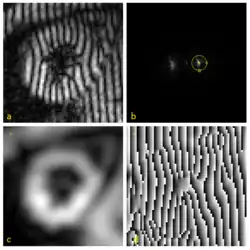

A tagged MRI showing motion of a human heart is shown in the image (a). The effect of tagging can be described as a multiplication of the underlying image by a sinusoid tag pattern having a certain fundamental frequency, causing an amplitude modulation of the underlying image and replicating its Fourier transform into the pattern shown in (b).

HARP processing uses a bandpass filter to isolate one of the spectral peaks. For example, the circle drawn in (b) is the -3 dB isocontour of the bandpass filter used to process this data. Selection of the filters for optimal performance is discussed in this paper.[14] The inverse Fourier transform of the filtered image yields a complex harmonic image at image coordinates and time :

where is called the harmonic magnitude image and is called the harmonic phase image. The harmonic magnitude image in (c) extracted from a using the filter in (b) shows the geometry of the heart. And the harmonic phase image in (d) contains the motion of the myocardium in horizontal direction. In practice, tagged images from two directions (both horizontal and vertical, i.e., is 1 and 2) are processed to provide a 2D motion map in the image plane. Notice that the harmonic phase images are computed by taking the inverse tangent of the imaginary part divided by the real part of , such that the range of this computation is only in . In other words, d is only the wrapped value of the actual phase. We denote this principle value by ; it is mathematically related to the true phase by: